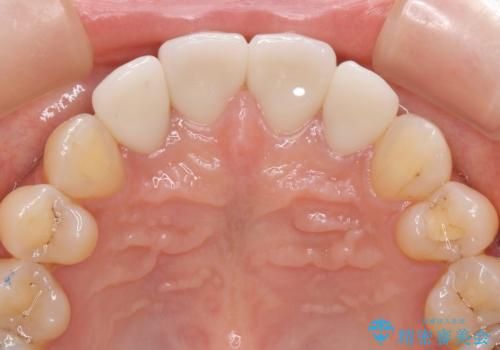

- 52.8万円(ジルコニアクラウン×4・仮歯×4)費用は治療当時の料金となります

自然な歯の仕上がりに満足いただくことができました。